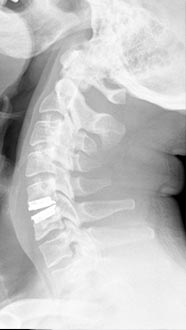

35 year old man presenting with severe neck pain with radiation down the right arm with right bicep weakness. MRI with large right C5-6 disc extrusion.

Postoperative xrays after C5-6 anterior cervical disc replacement. Complete resolution of arm pain and full painless range of motion of his neck.